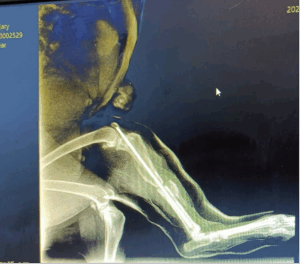

This report presents the successful management of a mid-shaft tibial fracture in an 8-year-old indigenous female dog weighing 15.6 kg in a private clinic, Indore, (M.P). The dog exhibited non-weight-bearing lameness in the affected limb. Surgical stabilization was performed using a 3.5 mm intramedullary pin, following aseptic bone preparation with transverse flattening of the fracture ends. The procedure was conducted under balanced anaesthesia with Butorphanol, and Propofol, maintained with Isoflurane. Post-operative care included inj. Amoxicillin-Clavulanic acid, Meloxicam and regular antiseptic dressing. A fiber cast was applied to control axial rotation. The dog recovered fully within 40 days.

An 8-year-old indigenous female dog (Desi breed) weighing 15.6 kg was presented with an inability to bear weight on the right hind limb. Clinical and radiographic examination confirmed a mid-shaft tibial fracture. Due to the severity of the fracture, surgical stabilization was deemed necessary.

- Intramedullary Pinning: A 3.5 mm intramedullary pin was inserted using a retrograde approach, followed by normograde placement for enhanced stability.

- Wound Closure and Casting: The surgical site was closed using absorbable and non-absorbable sutures in a routine manner. A fiber cast was applied to immobilize the limb while keeping a window at the wound site for dressing. The cast was maintained for 12 days to prevent axial rotation and allow proper healing.